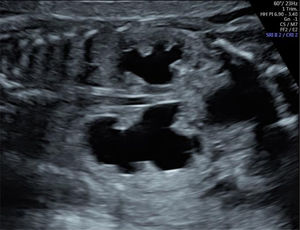

El diagnóstico diferencial de DTU depende en gran medida de la localización y del grado de dilatación dentro del tracto urinario. La hidronefrosis sin hidrouréter puede indicar una obstrucción de la unión pieloureteral (UPU) (fig. 4), mientras que la dilatación de la pelvis renal con hidrouréter sugiere más probablemente un reflujo vesicoureteral (RVU) o una obstrucción de la unión vesicoureteral (fig. 5). Además, una hidronefrosis severa puede, en ocasiones, simular RDMQ; por lo tanto, este último debe incluirse en el diagnóstico diferencial. Dado que un sistema colector renal duplicado puede asociarse con hidronefrosis en una o ambas porciones, se recomienda una evaluación detallada del aspecto renal y la búsqueda de un ureterocele en la vejiga. La dilatación de todo el sistema (riñón, uréter y vejiga) indica una obstrucción congénita del tracto urinario inferior (fig. 6), que puede tener diversas etiologías, como válvulas de uretra posterior (en fetos masculinos), atresia uretral o malformaciones cloacales (en fetos femeninos)19. Con excepción de la pielectasia transitoria, siempre se ofrece evaluación genética prenatal ante la sospecha de DTU fetal.

Obstrucción del tracto urinario inferior alrededor de las 23 semanas de edad gestacional. Obsérvese la hidronefrosis bilateral, más prominente en uno de los dos riñones. La vejiga también está agrandada (no visible en esta imagen). Imagen ecográfica del Centro Médico de la Universidad Erasmus.